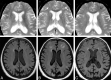

Background and purpose: AD is one of the few leading causes of death without a disease-modifying drug; however, hopeful agents are in various phases of development. MR imaging abnormalities, collectively referred to as amyloid-related imaging abnormalities, have been reported for several agents that target cerebral Aβ burden. ARIA includes ARIA-E, parenchymal or sulcal hyperintensities on FLAIR indicative of parenchymal edema or sulcal effusions, and ARIA-H, hypointense regions on gradient recalled-echo/T2* indicative of hemosiderin deposition. This report describes imaging characteristics of ARIA-E and ARIA-H identified during studies of bapineuzumab, a humanized monoclonal antibody against Aβ.

Results: Thirty-six patients were identified with incident ARIA-E (17.1%, 36/210) and 26 with incident ARIA-H (12.4%, 26/210); of those with incident ARIA-H, 24 had incident microhemorrhages and 2 had incident large superficial hemosiderin deposits.

Conclusions: In 49% of cases of ARIA-E, there was the associated appearance of ARIA-H. In treated patients without ARIA-E, the risk for incident blood products was 4%. This association between ARIA-E and ARIA-H may suggest a common pathophysiologic mechanism. Familiarity with ARIA should permit radiologists and clinicians to recognize and communicate ARIA findings more reliably for optimal patient management.